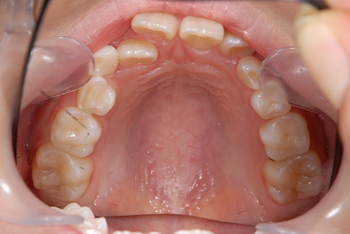

Before

小さい頃から通って頂いている患者様です。大きくなるに連れ、前歯の歯並びが特に気になりだしたということで、ご両親ともカウンセリングにお越しいただき、現状と今後についてしっかりお話させて頂いた結果、矯正治療をスタートすることになりました。